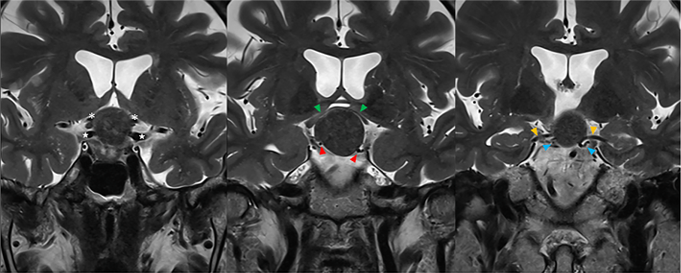

2020年,林女士像往常一样运动,突然一阵天旋地转,左腿像被电击般剧痛。急诊MRI提示:脑干海绵状血管瘤伴卒中出血。...